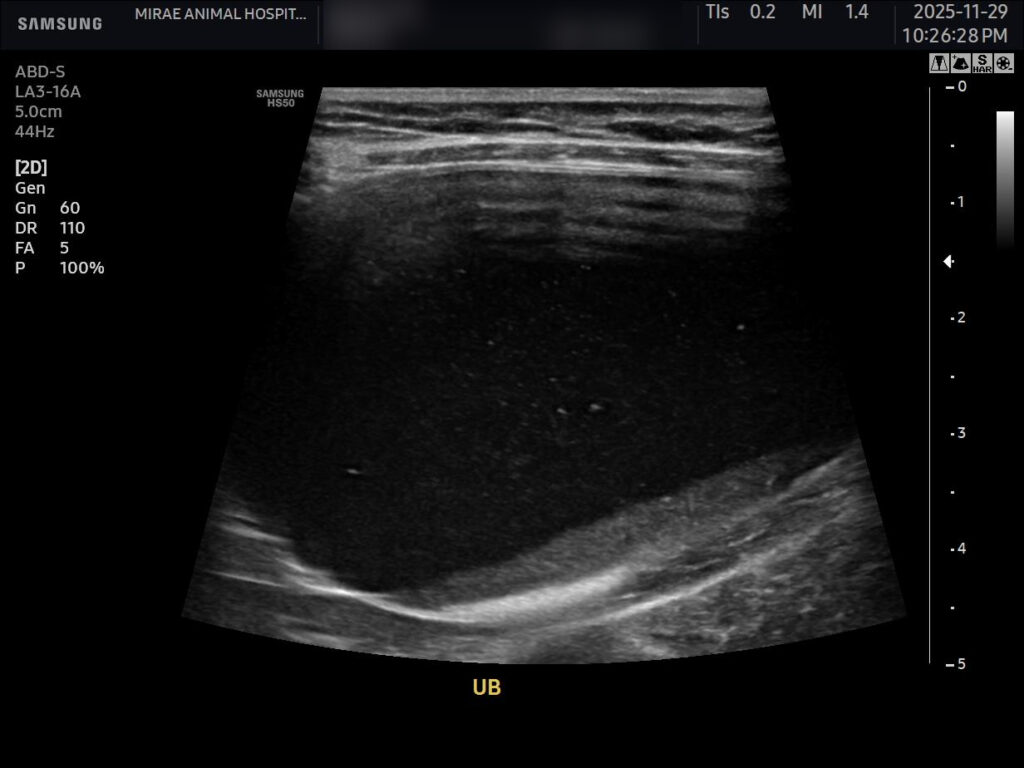

이어 시행한 초음파 검사에서는 방광 내부에 슬러지가 다량 관찰되었고, 중력 방향으로 가라앉아 있는 모습이 뚜렷했습니다. 또한 요도가 확장되어 있었고, 요도 쪽으로도 슬러지가 있는 상태가 확인되었습니다. 다행히 양쪽 신장은 양호한 상태로 확인되었습니다.

환자 초음파 사진/ 출처: 미래동물의료센터